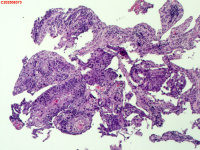

性别

男

年龄

40岁

临床诊断

肺癌?

一般病史

增强CT提示右肺中叶粘液栓;气管镜见右肺中叶外侧段新生物,考虑恶性可能。

图3

鳞状细胞癌